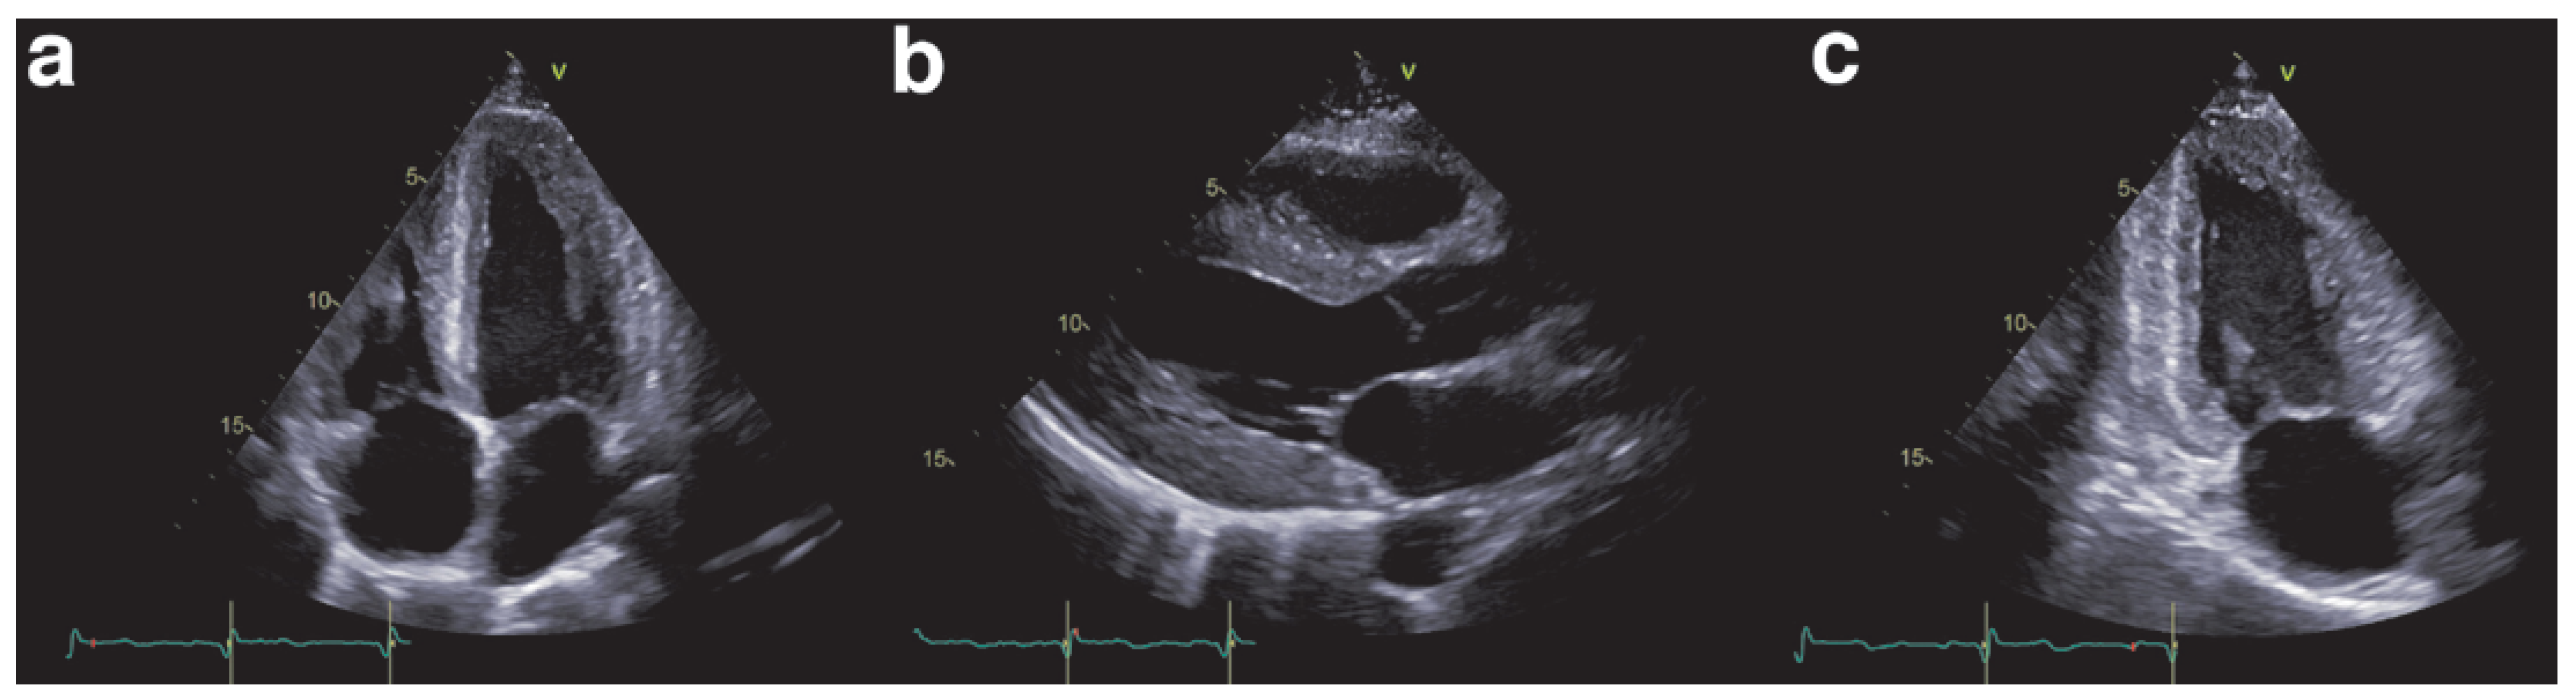

How do we diagnose cardiac amyloidosis?